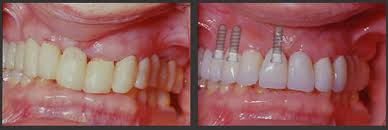

Αποτελούν την πιο σύγχρονη λύση για την αντικατάσταση των δοντιών που λείπουν. Πρόκειται για κατασκευές από τιτάνιο ως επί το πλείστον που τοποθετούνται, εν είδει βίδας, μέσα στο κόκαλο των γνάθων και έχουν το σχήμα της ρίζας του δοντιού. Εμφύτευμα, δηλαδή, ονομάζουμε τη «ρίζα» που φτιάξαμε, στην οποία στηρίζεται το υπόλοιπο δόντι, που είναι συνήθως από πορσελάνη.

• Τα δόντια που κατασκευάζονται πάνω τους μοιάζουν φυσικά.

• Όταν λείπει ένα δόντι και ο γιατρός δεν θέλει να τροχιστούν τα γειτονικά ακέραια δόντια, προκειμένου να χρησιμοποιηθούν ως στηρίγματα γέφυρας.